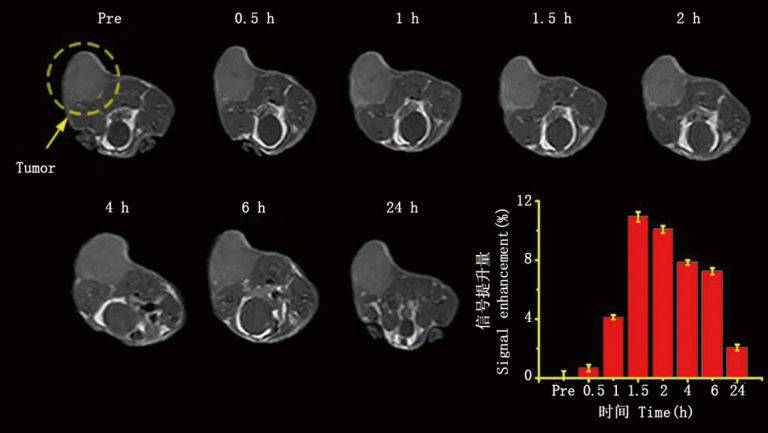

皮下腫瘤成像

小動物磁共振成像(MRI)是臨床前研究、藥物開發(fā)和小動物疾病模型的無創(chuàng)性體內(nèi)評價的有力方法。在臨床前研究中,活體MRI可用于縱向研究,以無創(chuàng)監(jiān)測疾病的進展、消退和治療過程。不需要在檢測時間點犧牲動物,同一動物可以在疾病發(fā)展過程中不同階段進行成像,從而排除個體差異。